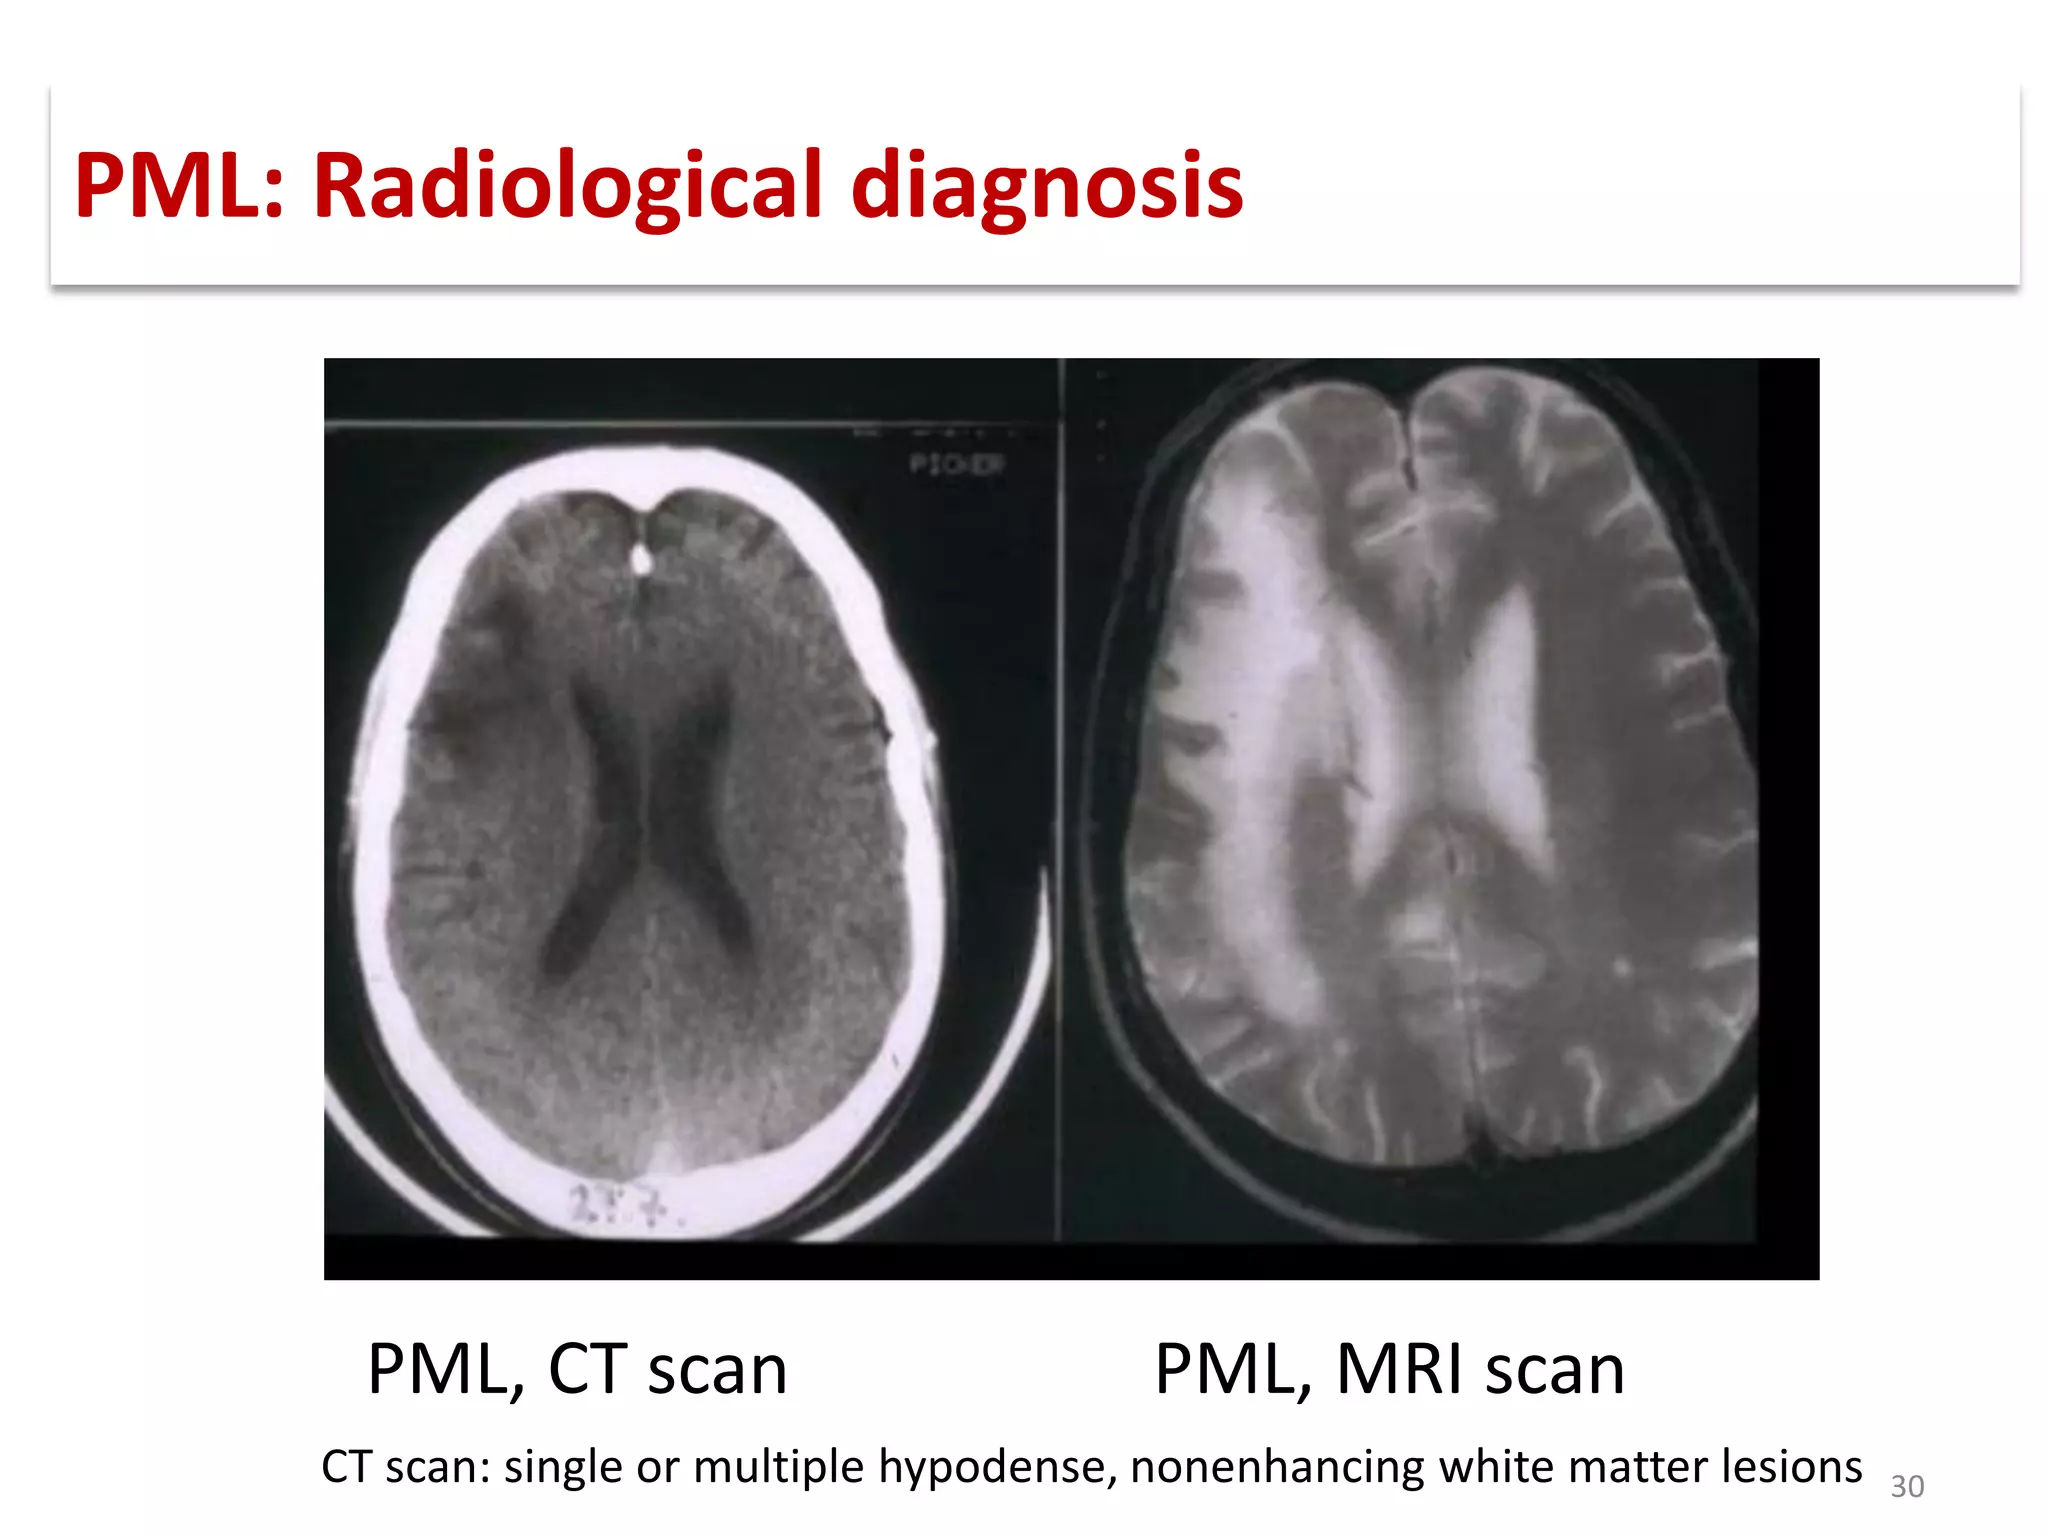

This document discusses progressive multifocal leukoencephalopathy (PML), an opportunistic infection caused by the John Cunningham virus (JCV) that leads to demyelination in the central nervous system. It highlights the epidemiology, clinical manifestations, diagnostic methods, and risk factors associated with PML, particularly in immunocompromised patients and those undergoing immunomodulatory therapies. It also presents data on the incidence of PML in patients treated with natalizumab and other therapies, addressing the relationships between these treatments and the development of PML.